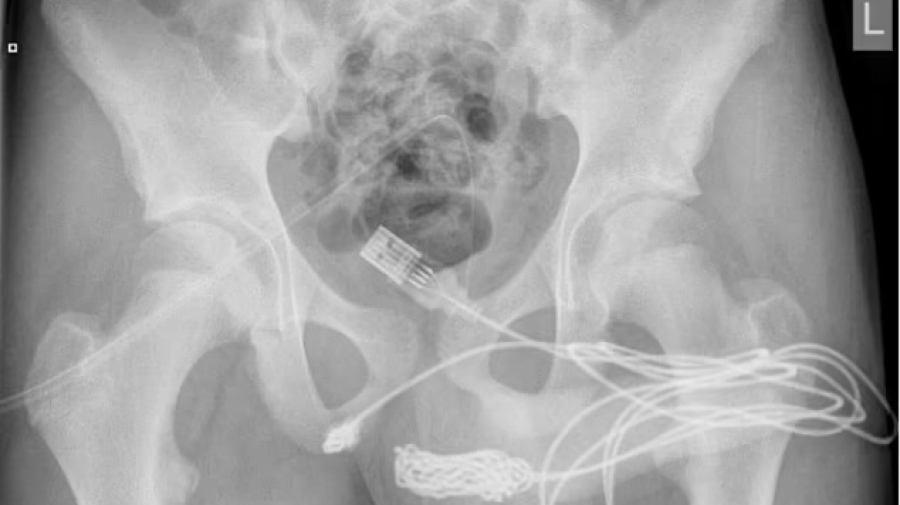

Μετά από μια ακτινογραφία που αποκάλυψε το μέγεθος και τη θέση του, ο έφηβος μπήκε στο χειρουργείο. Τελικά, ύστερα από μια δύσκολη προσπάθεια, αφαιρέθηκε

Οι εργαζόμενοι στο νοσοκομείο δεν κατάφεραν επίσης να αφαιρέσουν το καλώδιο με τη χρήση ειδικών εργαλείων εξαιτίας της θέσης του, όπως ανέφεραν οι γιατροί στο Urology Case Reports. Το παιδί μεταφέρθηκε τότε εσπευσμένα στο University College Hospital του Λονδίνου.

Μετά από μια ακτινογραφία που αποκάλυψε το μέγεθος και τη θέση του, ο έφηβος μπήκε στο χειρουργείο. Τελικά, ύστερα από μια δύσκολη προσπάθεια, αφαιρέθηκε.